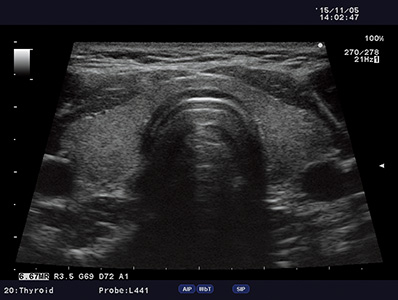

eFocusing is a transmission and reception technology to achieve clarity of imaging from near to far field. Reduced focus dependency and patient dependency.